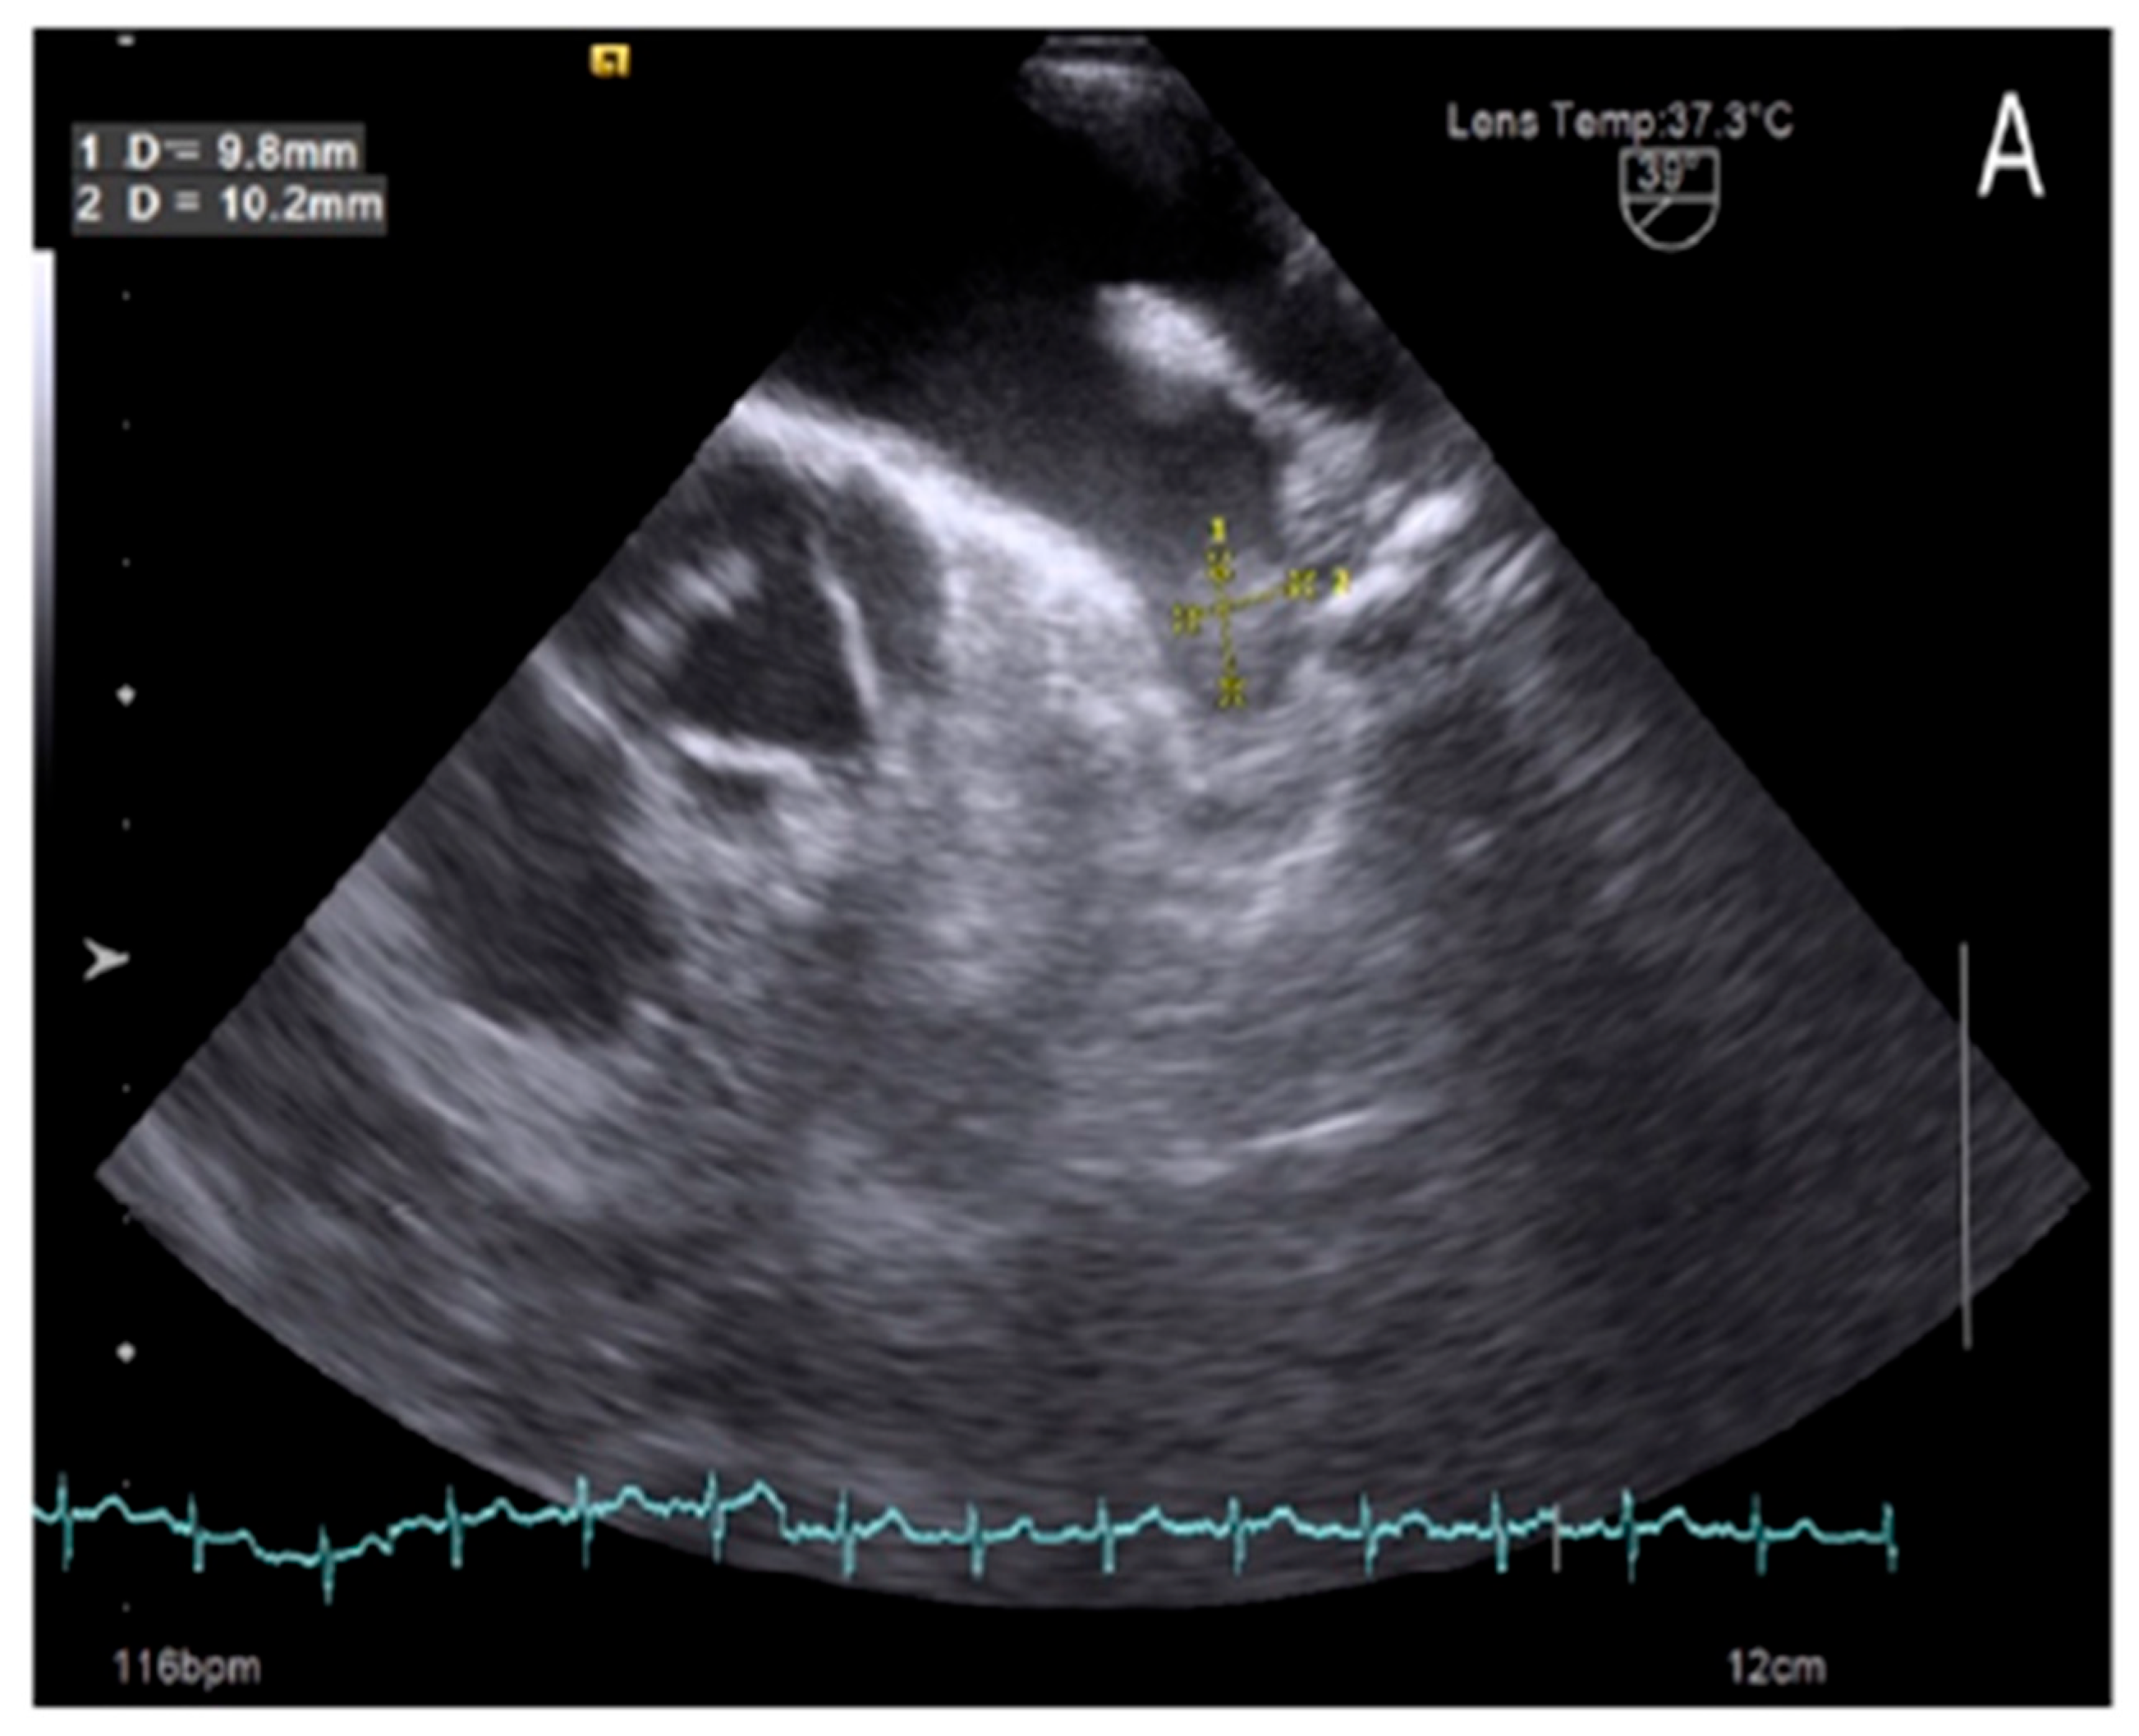

Our study also found that 7 out of 152 patients in sinus rhythm (Figure 1) had LAA thrombus, accounting for 4.6%, despite comprehensive evaluations using surface electrocardiography (ECG) and 24 to 48 h Holter ECG monitoring. The occurrence of thrombus in patients with sinus rhythm has gained increasing attention, as recent studies suggest that LAA thrombus formation is not solely attributed to atrial fibrillation but is also influenced by other factors, such as ischemic atrial cardiomyopathy, LAA dysfunction, and LAA deformation [14,16]. Collectively, these factors contribute to a higher incidence of LAA thrombus in patients with sinus rhythm.

Figure 1. Left atrial appendage thrombus on transesophageal echocardiography images in patient with sinus rhythm.